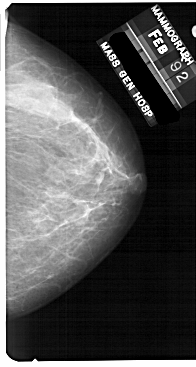

A_1710_1.LEFT_MLO

LEFT_MLO LINES 5491 PIXELS_PER_LINE 3376 BITS_PER_PIXEL 12 RESOLUTION 43.5 OVERLAY